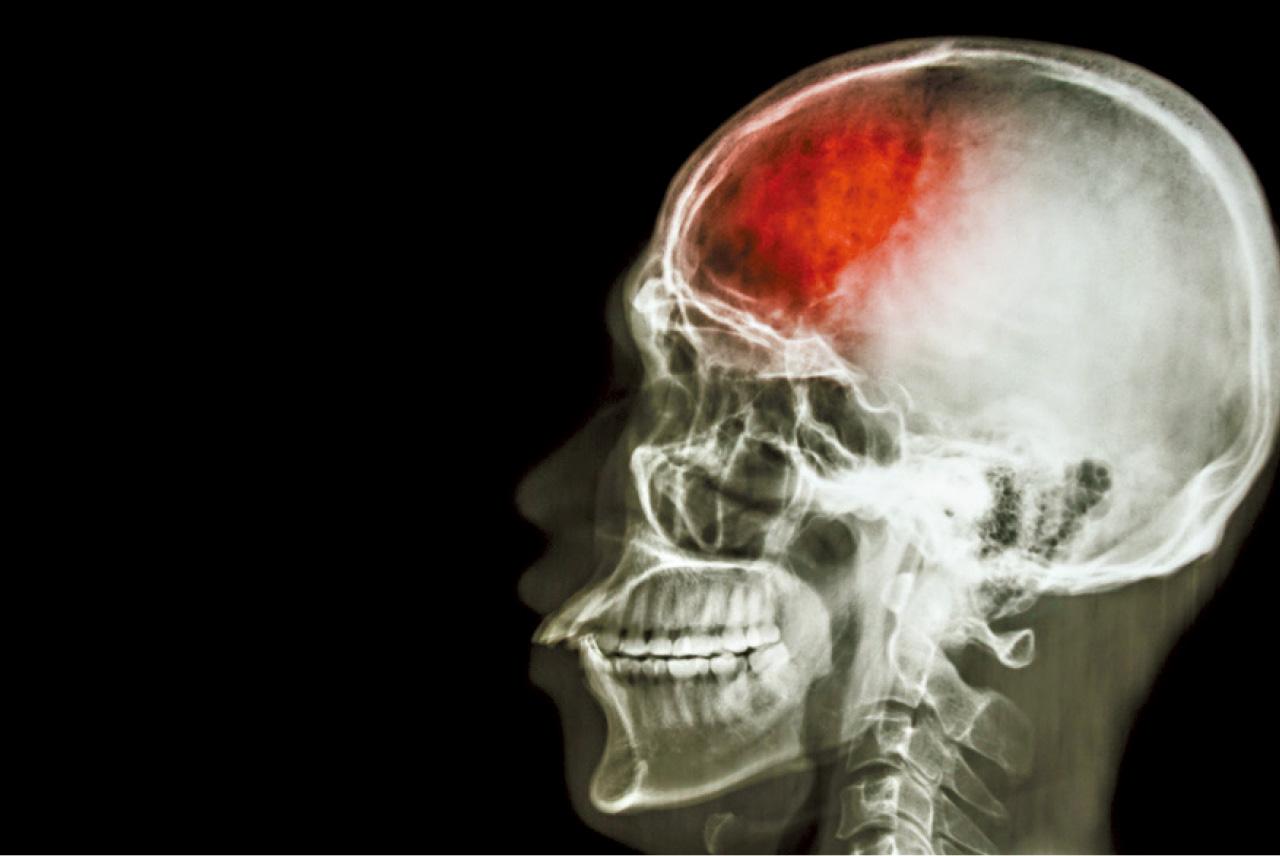

當心房顫動時,血液流動減慢,便會形成血塊,若血塊經過血管流至腦部,會阻塞血流,導致中風。

「房顫被稱為隱形殺手,因為超過一半的患者並無明顯症狀。」黃文灝強調,許多患者可能在健康篩查或例行檢查中才發現心房顫動。若有症狀,則可能出現心悸或心跳不規則,但這些情況並不常見。心房顫動患者中風的風險比普通人高出5倍。黃文灝指出,「當心房顫動時,心臟跳動不規則,血液流動減慢,心房便會形成血塊。這些血塊若經過血管流至腦部,會阻塞血流,導致中風。」